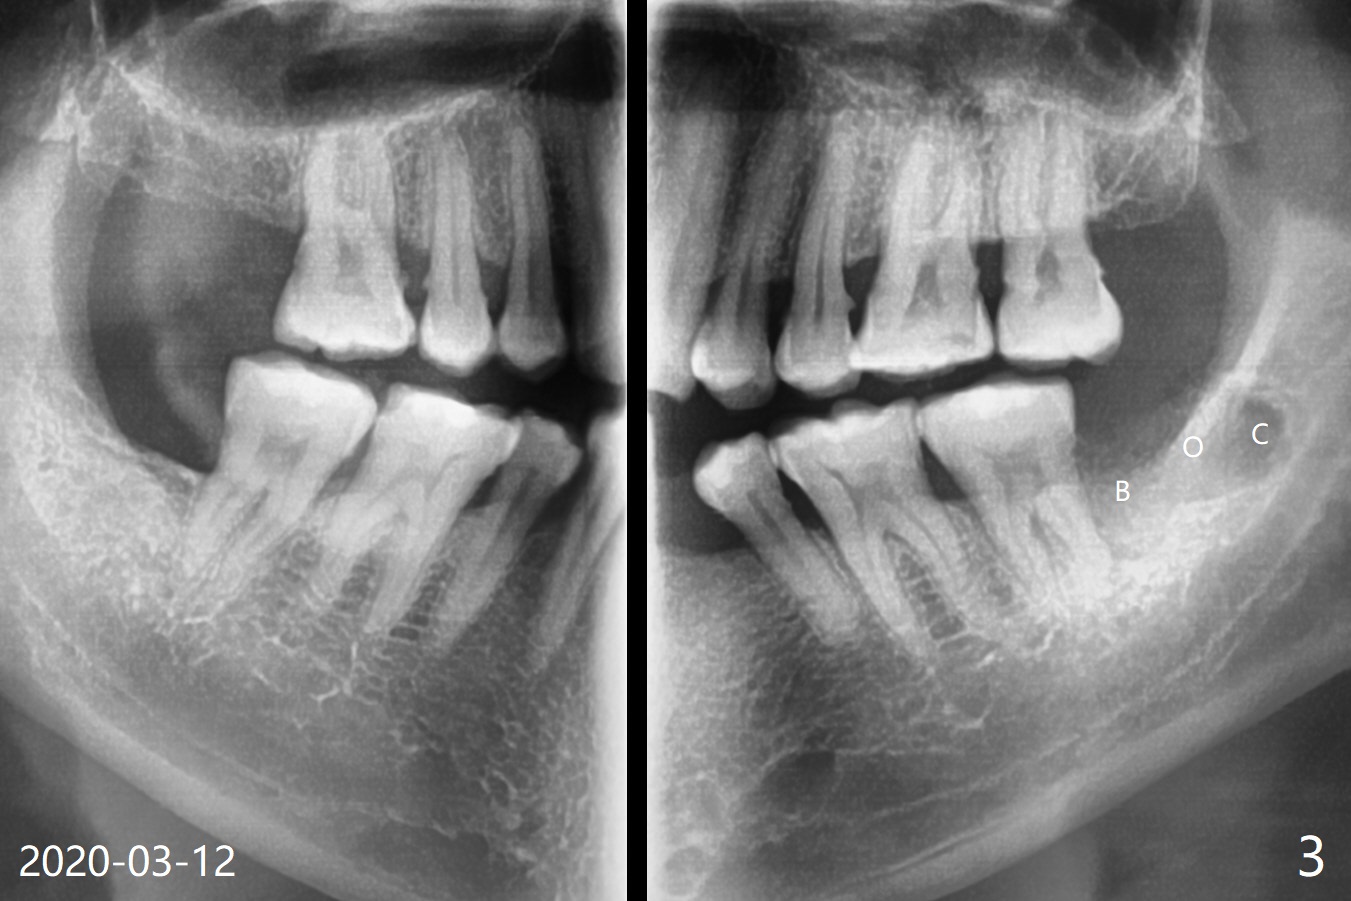

A 51-year-old man returns for #17 extraction 3.5 years post #32 one (Fig.1,2). The bone distal to #18 is lost severely (Fig.1). After #17 extraction and granu-lation tissue removal, Collagen Plug (Fig.3 C), Osteogen Plug (O) and cortical: cancellous (50: 50) mine-ralized allograft (.5-1 mm) saturated with ~ .2 ml of .3 mg/ml of rhPDGF-BB (B, one component of GEM21S) is placed in the socket. The patient returns with chief complaint of referring pain to the left ear 6 days postop, although the extraction wound looks fine. The mild pain (controlled by pain medication) persists 10 days and 1 month postop. The pain 1 month postop is associated with mastication. It appears that the tooth #18 is periodontally compromised. Occlusal equilibrium is required.